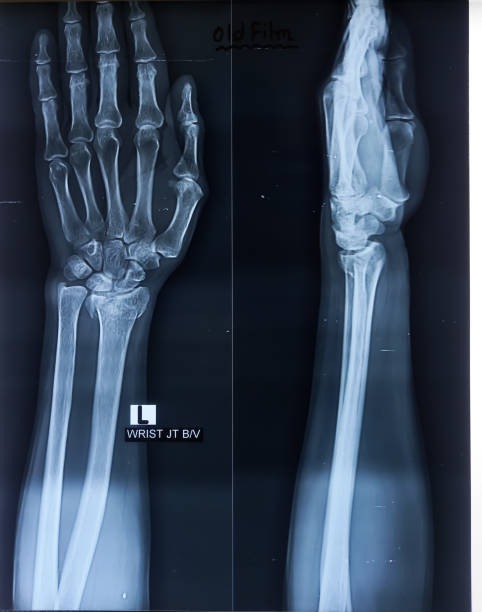

해부학적 이상은 척골충돌증후군의 주요 원인 중 하나로, 팔꿈치와 손목 사이의 뼈 구조나 관절 배열에 선천적 혹은 후천적 변형이 있을 때 발생할 수 있습니다. 예를 들어, 척골이 정상보다 길거나 뼈의 돌출부가 비정상적으로 발달하면 손목과 척골 사이의 공간이 좁아져 충돌이 발생하기 쉽습니다. 이런 구조적 이상은 일상적인 움직임에서도 반복적으로 뼈와 인대, 힘줄 사이에 마찰을 일으켜 염증과 통증을 유발합니다. 해부학적 이상은 개인마다 다르게 나타나며, 증상이 심하면 기능 저하와 만성 통증으로 이어질 수 있습니다. 정확한 진단을 위해 X-ray, MRI 등의 영상 검사가 필요하며, 치료는 보존적 방법부터 수술적 교정까지 다양하게 적용됩니다. 조기에 이상을 발견하고 적절한 관리와 운동으로 관절의 움직임을 개선하는 것이 중요합니다.

손목 및 팔꿈치 외상은 척골충돌증후군 발생에 중요한 역할을 합니다. 넘어지거나 충격을 받았을 때 손목이나 팔꿈치에 직접적인 타격이 가해지면 뼈나 연골, 인대가 손상될 수 있습니다. 이러한 외상은 관절 내 공간을 좁히거나 염증을 유발해 척골과 손목뼈 사이의 충돌 가능성을 높입니다. 특히 골절 후유증이나 인대 파열은 관절 안정성을 떨어뜨려 반복적인 마찰로 만성적인 통증과 운동 제한을 초래할 수 있습니다. 외상 후 적절한 치료와 재활이 이루어지지 않으면 척골충돌증후군으로 진행될 위험이 높아집니다. 따라서 초기 외상 발생 시 전문의의 정확한 진단과 치료, 꾸준한 물리치료가 중요하며, 손상 부위의 기능 회복과 통증 완화에 초점을 맞추는 것이 필요합니다.

골절 후유증은 뼈가 부러진 후 적절히 치유되지 않거나 회복 과정에서 문제가 생겨 나타나는 다양한 합병증을 의미합니다. 골절 부위가 제대로 맞지 않으면 변형이 발생하거나, 뼈가 유합되지 않는 불유합 상태가 될 수 있으며, 이는 통증과 기능 저하를 초래합니다. 또한 주변 인대나 근육, 신경 조직이 손상받아 운동 범위 제한과 근력 약화가 나타나기도 합니다. 특히 관절 근처 골절의 경우 관절 기능 장애가 심해지기 쉬워 일상생활에 큰 불편을 줄 수 있습니다. 감염이나 혈액 공급 장애로 인한 골괴사도 후유증으로 발생할 수 있으며, 재활 치료와 지속적인 관리를 통해 기능 회복을 도모해야 합니다. 골절 후유증을 예방하려면 초기 적절한 치료와 꾸준한 물리치료, 그리고 정기적인 추적 검사가 필수적입니다.